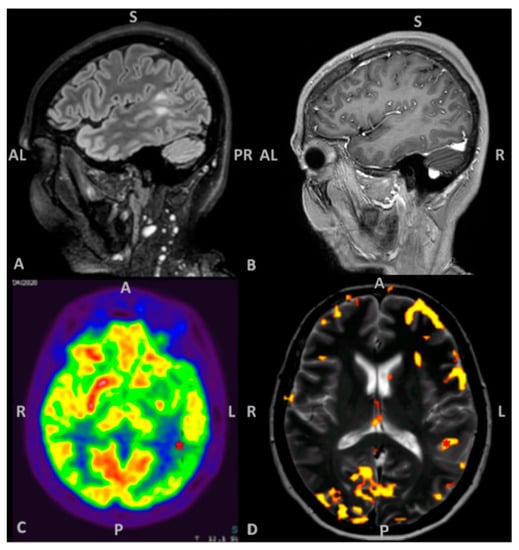

2.1. Patient Information, Clinical and Radiological Findings

2.4. MRI Acquisition